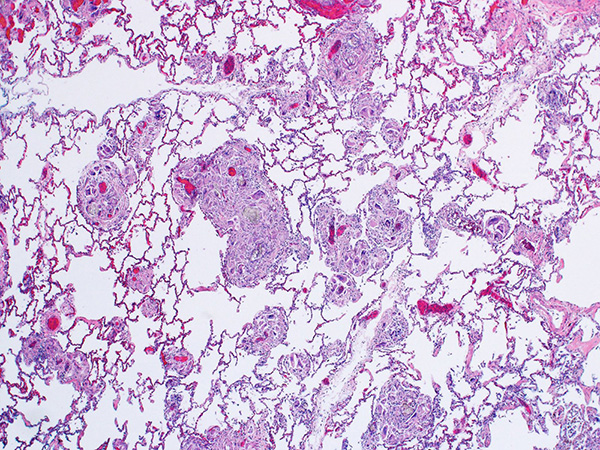

Clinical History:A 42-year-old man presented with increasing dyspnea. Chest CT at an outside institution reportedly showed “interstitial micronodular disease.” An open lung biopsy was performed (Figures 1-6; Fig. 6 under polarized light).

The current case shows patchy nodular expansion of the interstitium by foreign-body giant cells (Figures 1 and 2). The giant cells are located adjacent to small blood vessels in the interstitium, and contain microcrystalline cellulose and crospovidone particles (Figures 3-6). Microcrystalline cellulose particles are large, elongated, rod-like pale-gray crystals on H&E, measuring up to 250 μm in length. They show strong birefringence under polarized light (Figures 4-6). Crospovidone has a deeply basophilic or deep purple coral-like appearance and is not birefringent. It is seen at bottom right in Figures 5 and 6. Talc particles, when present, are smaller (6-23 μm) and sheet-like with a slight yellow hue on H&E and strong birefringence under polarized light.